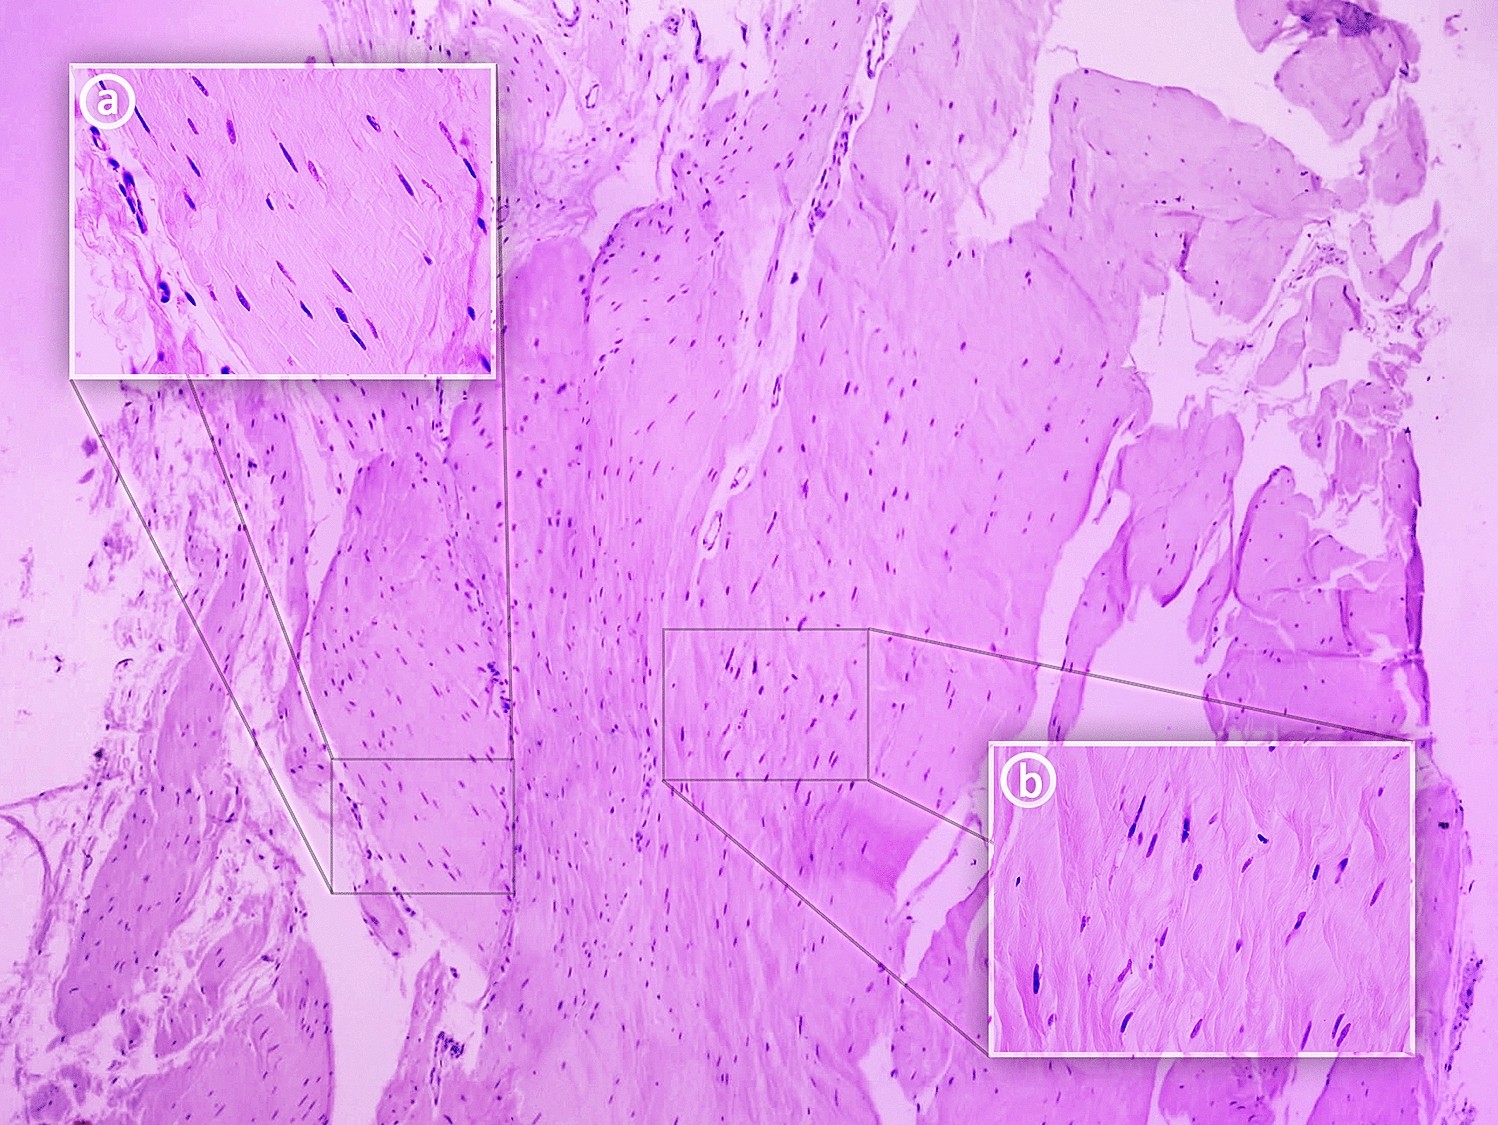

Histological examination of the plantaris ligamentous tendon. (a) 400 × magnification—tendon; (b) 400 × magnification—ligament.